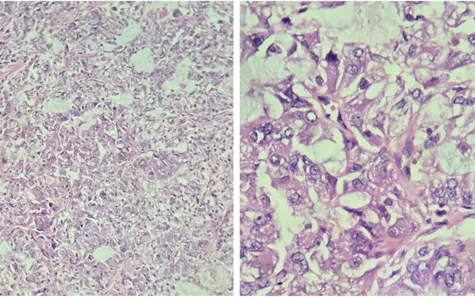

Kết quả cho thấy mô học hoàn toàn khác với tổn thương ở trực tràng, giúp loại trừ khả năng di căn. Sau khi thực hiện thêm hóa mô miễn dịch và khảo sát các tuyến nước bọt không phát hiện tổn thương, các bác sĩ hướng đến chẩn đoán carcinoma tế bào túi tuyến nguyên phát tại phế quản.

Bệnh nhân sau đó được phẫu thuật cắt bỏ khối u. Kết quả mô bệnh học trên mẫu bệnh phẩm sau mổ hoàn toàn phù hợp với chẩn đoán này.